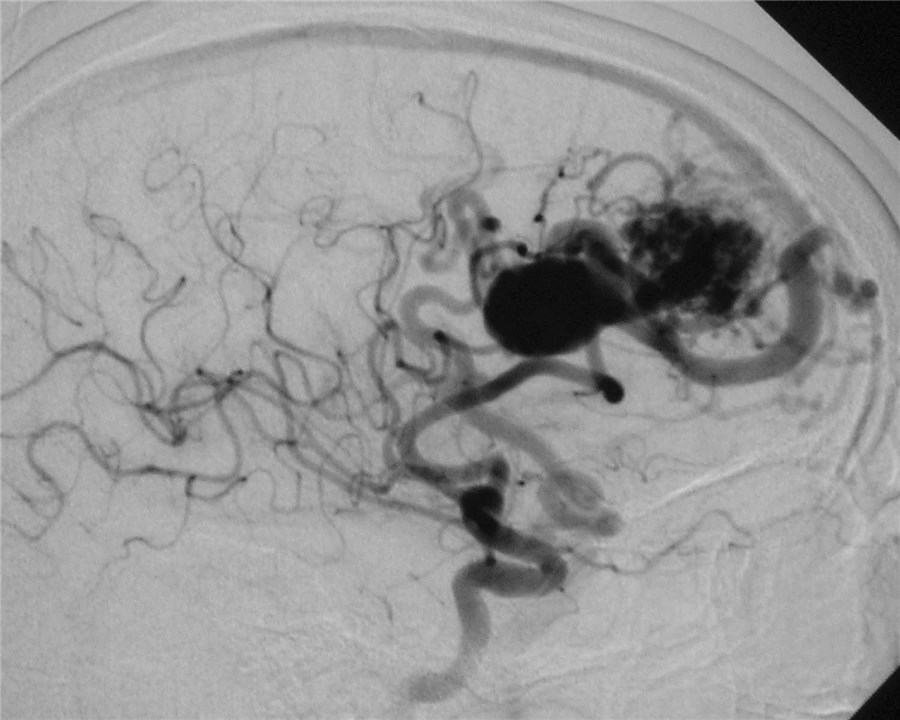

Arteriovenous malformations

Arteriovenous malformations of the brain are abnormal bunch of blood vessels that can rupture causing bleeding, or may cause seizures. Brain imaging (CT, MRI) is required for early diagnosis, while definitive treatment is carried out after cerebral angiography. Treatment implies craniotomy and excision of the AVM, which can be done safely in majority of the cases. Embolisation and radiosurgery are acceptable substitutes, but carry risk of further bleeding.